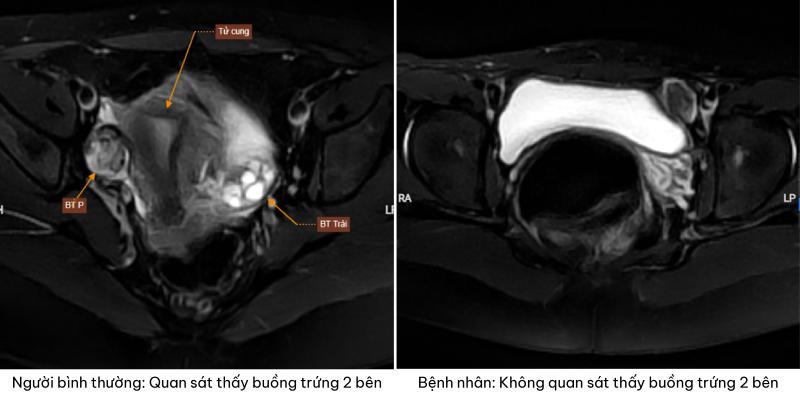

Kết quả siêu âm và chụp cộng hưởng từ cho thấy một thực tế khiến cả gia đình bàng hoàng: không phát hiện hình ảnh tử cung và buồng trứng ở cả hai bên.

Trên hình ảnh chụp cộng hưởng từ phát hiện bệnh nhân không có tử cung và buồng trứng hai bên